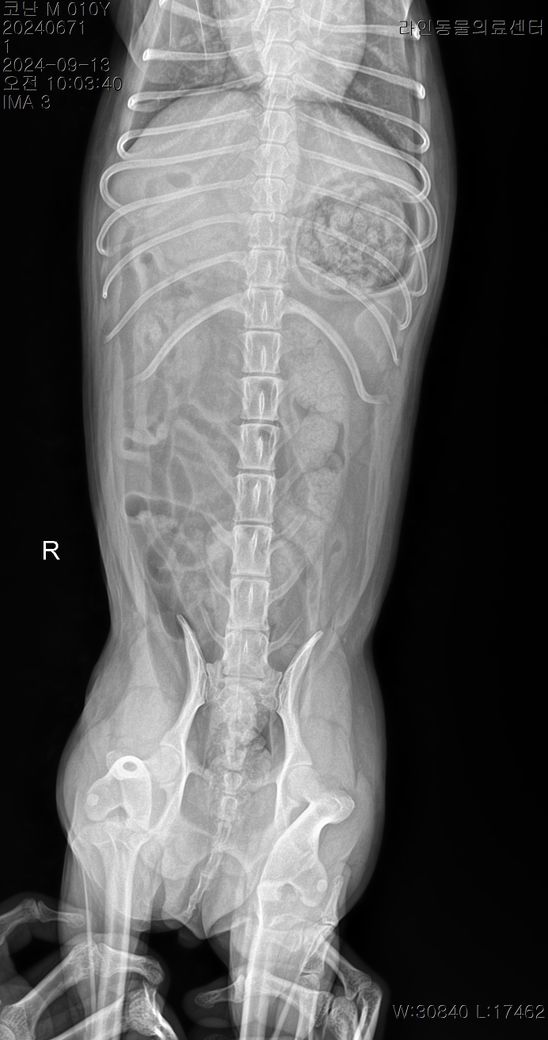

선생님 저희 강아지 허리디스크가 어느정도인가요?

한달에 한번 주기로 깨갱 거리면서 특히나 혼자 붕가붕가하고 나서 그러는데요

허리 디스크가 어느정도 상태인지 그리고 붕가붕가를 평생 못하게해야하는건지.. 알려주시면 감사하겠습니다....

경추와 흉요추부에 디스크 소인이 있는 양상이 관찰되고 있지만 디스크는 엑스레이 사진으로 평가하는 질환이 아닙니다.